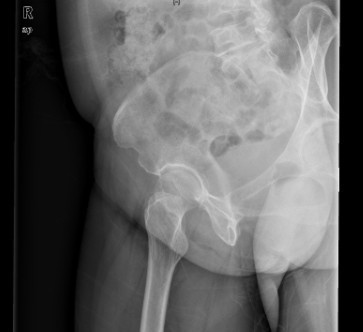

患者女,61岁,因“摔伤致右髋关节疼痛、活动受限9小时”入院。患者于入院前9小时行走时不慎摔倒,右侧肢体着地,当即感右髋关节及右大腿上段疼痛,活动受限,不能自行站立,受伤时及伤后无昏迷,无恶心、呕吐,无心累、气促,无腰痛及肉眼血尿。因休息后无缓解,急诊到当地医院行骨盆平片提示“右股骨颈骨折”,未做任何治疗,患者为求进一步治疗,遂急诊来我院,急诊以“右股骨颈骨折”收入住院。

查体:右髋关节、右大腿皮肤完整性好,右下肢轻度外旋。右腹股沟中点压痛明显,右股骨无明显压痛,未扪及明显骨擦感。右髋关节主被动活动受限。右下肢较左下肢短缩1cm。 辅查:院外X片右股骨颈骨折。

诊断:1、右股骨颈骨折(Garden III);2、骨质疏松症 治疗:择期手术